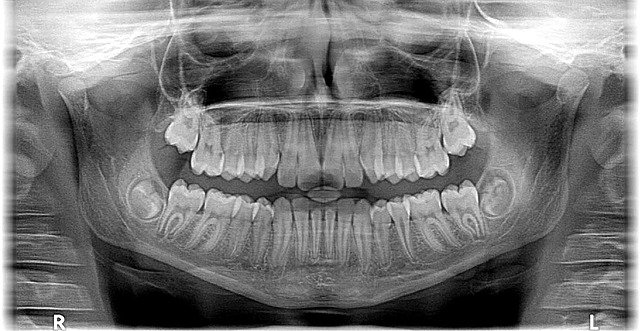

Tanto chicos como adolescentes, están en constante crecimiento, por lo tanto es importante mantenerlos en revisión continua para analizar factores como, por decir algunos ejemplos, el tipo de mordida que tienen, asegurarnos que estén libres de caries y, en el caso de adolescentes, asegurarnos de que las muelas del juicio no se conviertan en una pesadilla en el futuro.